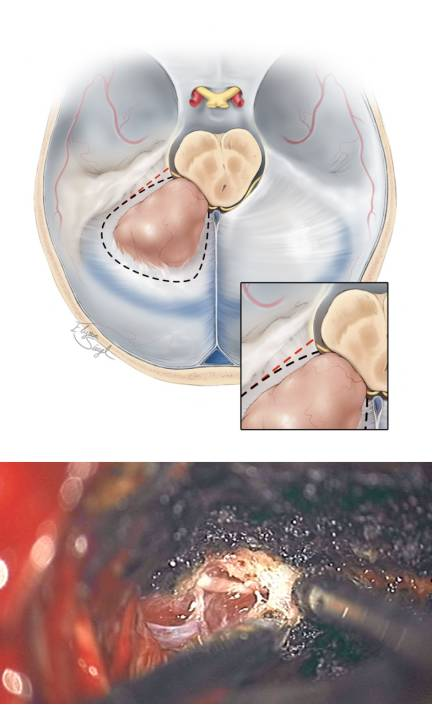

图9. 在切除天幕游离缘的时候要注意保护滑车神经(上方插图)。若要沿着红色虚线切除将会损伤神经,而沿着黑色虚线则利于神经保护。另外,颞叶后方基底部的脑实质肿瘤需要T形切口切开天幕。切除左侧岩骨天幕区域脑膜瘤的术中图片证实了滑车神经在肿瘤和天幕前缘进入硬模(下图)。

图10. 在充分保护滑车神经的情况下,天幕切口可从岩骨边缘延伸直到中线以包含肿瘤基底区域。在少数情况下,如术中发现汇入天幕的枕叶引流静脉阻挡视野,可将其牺牲。沿中线切开天幕时必须注意保护直窦以及其分支。天幕有可能存在静脉湖,而天幕的静脉出血可以通过浸泡凝血脢的明胶海绵压迫止血,而双极电凝则会皱缩天幕,扩大裂口而加重出血。